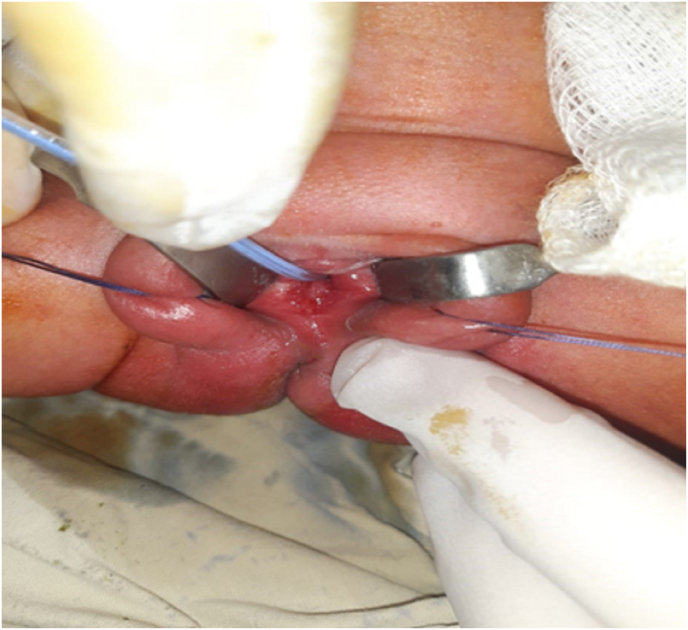

She was treated with ultrasound-guided aspiration of HMC and approximately 1 L of fluid was drained. Respiratory effort improved after fluid aspiration and a temporary drain was left inside for decompression and she has normal genitalia (Fig. 3). The pediatric surgeon discharged the patient after seven days. Her HMC decreased in size and the patient was doing well on follow-up. Informed consent was taken from the parents for the case report. SCARE guidelines followed in reporting the case [5].

Fig. 3.

Normal genitalia seen after decompression of uterus.